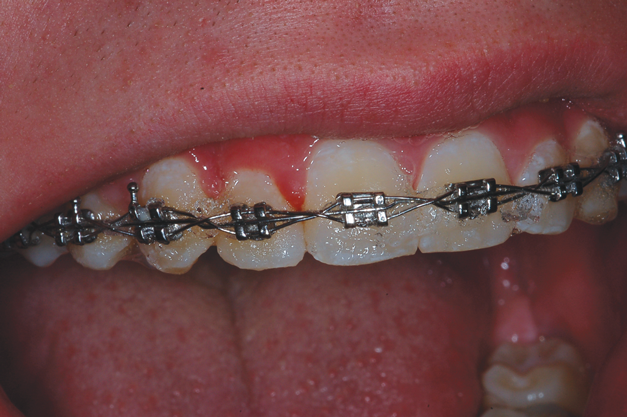

One of the biggest challenges for teenagers wearing braces is the time that it takes for proper oral hygiene to avoid white spot lesions and active caries.12 Furthermore, their eating habits and lifestyle do not always support good hygiene practices. Research indicates that the use of 10% carbamide peroxide for bleaching results in a reduction of caries because it creates a more basic oral environment with a pH greater than 8.0 within 5 minutes after insertion,13 removing plaque and killing bacteria that cause tooth decay.14 Therefore, tray application of carbamide peroxide has been recommended for elderly and special needs patients with root caries when fluoride trays are ineffective.2,15 It can also provide caries control benefits for patients with orthodontia.

For orthodontic patients, the single clear tray used is 1.5-mm thick. Due to its thickness and the presence of the orthodontic brackets, the dentist takes a more active role in molding this clear tray intraorally. The tray is heated in the same manner as the previously discussed thermoplastic trays. Even when completely softened, it will not become imbedded into the brackets. When seating it, the path of insertion into the mouth should be slightly more facial to avoid engaging the tray edges on the brackets. The dentist must act quickly to seat the tray intraorally and begin applying pressure on the walls from the anterior to the posterior segments to adapt the tray over the brackets and onto the gingiva before it cools. As before, the patient will bite on his or her back teeth and produce suction to create a vacuum. When the tray has lost its heat, it is removed from the mouth, and the handle is removed with crown and bridge scissors. The patient or dentist may initially experience difficulty in determining the seat of the tray because the tooth molds are not as pronounced due to the presence of the orthodontic appliance. However, the tray will have a definite seat and fit once the path of insertion is found, and the patient should be able to insert and remove it easily (Figure 9).

For bleaching treatment, the carbamide peroxide is injected into the tray via the trough created by the arch wires and brackets, and then the tray is inserted into the mouth. Typically, more bleaching material is used with this treatment in order to fully penetrate the wires and brackets to mechanically and chemically clean the braces (Figure 10). It is recommended that patients wear the tray while sleeping because of the reduction in saliva flow that happens nocturnally. A new tray will need to be made about every 3 to 4 months due to the shifting of the teeth, but this soft tray will not impede the progress of the orthodontics. The tray is difficult to fabricate on the mandibular arch because it requires good tongue control by the patient to be successful. Although a conventional alginate impression could be made, it would require removing the arch wires each time, and it would not capture the gingiva as well as a tray made directly in the mouth.

Another preventive option involves injecting carbamide peroxide directly onto the braces prior to brushing (Figure 11), which immediately causes a foaming, bubbling action when the material comes into contact with plaque (Figure 12). The use of this approach to chemically clean the braces as well as the use of 3% over-the-counter hydrogen peroxide in a 1:1 ratio in a water pick is beneficial to preventing white spot lesions. The only side effect of using 10% carbamide peroxide with tray treatment for caries control is that the teeth will be bleached. This is generally a beneficial coincident with orthodontic treatment and can serve as a motivator for a teenager to wear the tray. The cost of this tray bleaching treatment is approximately $400 to $600 over the course of 2 to 3 years of orthodontic treatment, which is far less than the cost of multiple composite restorations should caries occur. Any concerns that there may be yellow spots on the bleached teeth after removal of the brackets are unfounded because the material penetrates the tooth structure to bleach under existing restorations and brackets (Figure 13 and Figure 14).16

(13.) Retracted view of a patient who had been using tray application of 10% carbamide peroxide for over a year to clean the braces as well as bleach the teeth.

Figure 13